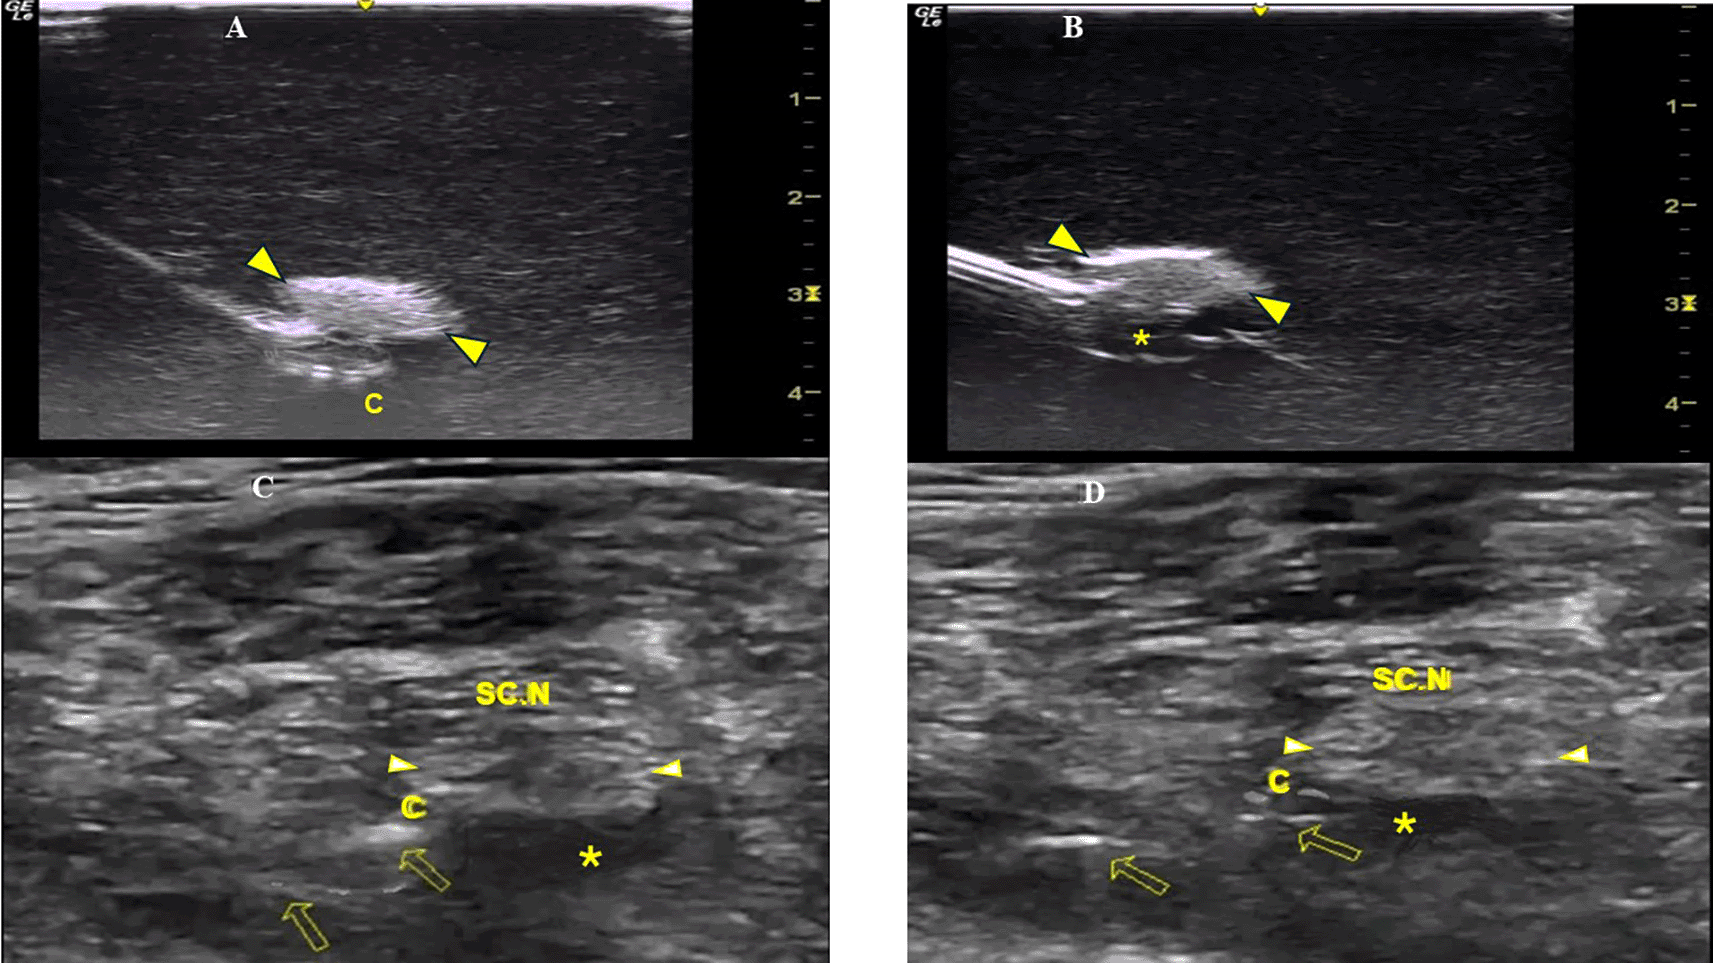

Method A: The catheter was advanced beyond the needle tip (under real-time US imaging) with its integral stylet extending along the entire length of the catheter (Figure 1A).

Inset: perineural catheter container. SC.N=Sciatic Nerve.

Method B: The catheter was advanced beyond the needle tip after the catheter’s integral stylet was retracted by 6 cm so that the catheter’s distal portion provided a more flexible end (Figure 1B).

The simulator was provided with a sciatic nerve insert (upper third of the posterior thigh) containing one nerve structure (CAE training Blue Phantom). The sciatic nerve-simulator surface distance featured different location depths (2-4 cm) (Figure 1C).

A Tuohy needle (18G × 7.5 mm, PAJUNK, Germany) was inserted at the simulator’s posterior thigh (TS) from a lateral to medial direction (needle in-plane/nerve in-short-axis technique). The needle insertion angles (coronal plane) were always kept at 40 degrees (Figure 1D). In both methods, the needle was aimed behind the sciatic nerve with the curved end facing the nerve (Figure 1E). The perineural catheter was threaded through the Tuohy needle until its tip reached the needle orifice. The catheter was slowly advanced exactly 6 cm (under real-time US guidance) beyond the curved tip of the Tuohy needle, until the catheter’s distal end-portion coiled exactly under the sciatic nerve (Figure 2A). To better visualize a catheter’s trajectory, a slight heel-toe maneuver was implemented to bring the US beam perpendicular to catheter’s distal portion. Procedural time was limited to 15 seconds (total allowed performance time for each coiling maneuver). Each attempt was stored digitally and analyzed off-line (frame by frame) by two co-investigators (EP, MR) who were blinded to group allocation. The two investigators decided independently whether the catheter coiled or not. The result was considered positive (coiled catheter) only after unanimous agreement between the two investigators. If the catheter distal end did not coil or if the catheter bypassed the nerve and then coiled, the catheter was withdrawn, the needle tip reoriented (rotation of needle shaft/tip at 90 degrees), and the catheter was readvanced. In total, three attempts were allowed (overall maximum procedural time: 45 seconds). The number of attempts to coil a catheter, as well as the proportion of cases where a catheter was successfully looped on first attempt, were measured. The patency of coiled catheters was tested after normal saline (3 ml) infusion through the catheter. Contact of saline spread with the nerve was also recorded (Figure 2B). All images were taken under the same imaging settings (gain: 90 db, focus position at the level of the nerve, standard time gain compensation).

C=Perineural Catheter, SC.N=Sciatic Nerve, *=LA spread.

Patients were placed in the lateral position (with the injured leg uppermost) and a US-guided sciatic nerve block was performed under aseptic conditions (TS, EP). The sciatic nerve was visualized at the upper third of the posterior thigh (short axis view) and a Tuohy needle (21 G × 10 mm, SonoLong/NanoLine, PAJUNK, Germany) was inserted in a lateral to medial direction. The needle was placed underneath the sciatic nerve and 10 ml of ropivacaine (0.1%) were injected. A perineural catheter (with retracted integral stylet by 6 cm) (SonoLong Sono, PAJUNK, Germany) was then threaded through the needle tip and coiled behind the sciatic nerve. Confirmation of correct catheter tip placement was defined as adequate spread and contact of ropivacaine injectate (3 ml, 0.1%) with the sciatic nerve (Figure 2C). If the distribution of the local anaesthetic (LA) could not be visualized on the first infusion, 2 additional injections were performed until the distribution was clearly seen. If LA spread could not be visually confirmed, or if, when confirmed, LA did not come in contact with the sciatic nerve, the case was excluded.

All CPNBs were assessed and data were collected in the post-anaesthetic care unit, and every 12 hours thereafter until 36 hours postoperatively from members of the acute pain service (APS) team not participating in the study. Observation of fluid under the dressing indicated catheter’s leakage. Unplanned external displacement and dislodgement of the catheter were defined: less than and equal to 6 cm (displacement) and more than 6 cm (dislodgement) movement of the catheter from the initial recorded depth at the point of insertion or from the distal end of the subcutaneous tunnel. The final catheter tip position was evaluated (under US imaging) 36 hours postoperatively and was identified by injecting 3 ml of ropivacaine (0.1%) through the catheter (Figure 2D). If LA spread was not confirmed after 3 injections or if, when confirmed, it did not come in contact with the sciatic nerve, the catheter’s tip was considered dislocated.